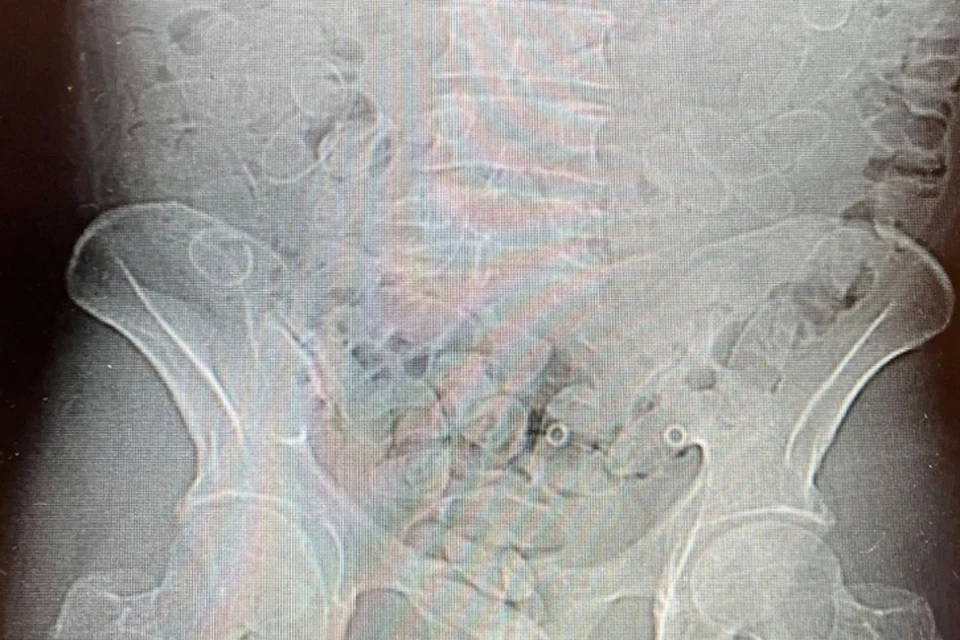

Компьютерная томография подтвердила наличие наркотиков

Также сотрудники отметили нервное поведение мужчины, которое могло указывать на то, что он перевозит наркотики. 40-летний пассажир сам признался в том, что проглотил запрещенные вещества. Его немедленно доставили в больницу, где компьютерная томография подтвердила наличие наркотиков в его организме. 89 капсул содержали в общей сложности около 0,8 кг кокаина. Мужчина арестован на три месяца по решению суда. Ему грозит до 20 лет лишения свободы за попытку контрабанды крупной партии наркотиков.